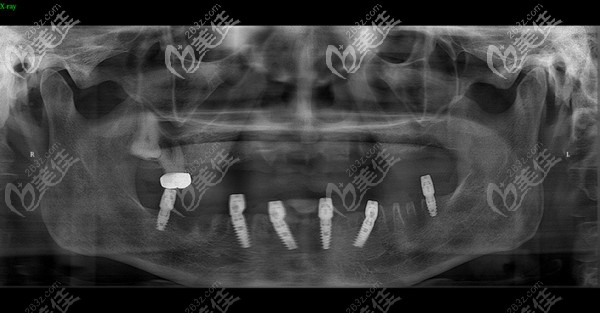

現(xiàn)在的全口種植牙無需28顆,基本上就是6-8顆就可以了,因此在選擇種植體材料上有了很多的空間,那要是選擇諾貝爾PCC種植牙一顆多少錢呢?

鄭州口腔種牙還挺靠譜,1年前做的Allon6現(xiàn)在吃東西依舊輕松 b588 G0 V0

其實做種植牙不怕花的錢多錢少,就怕的是花錢買罪受,比如術(shù)后基臺和種植體的密合性不好,長期如此引起能發(fā)炎疼痛。所以一定要找一家口碑好的醫(yī)院做種植,就像鄭州金水區(qū)的口腔,